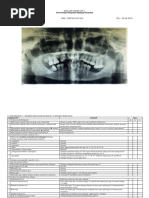

No. Radiograf 20190527104715378 Tanggal Pemotretan 5/27/2019

Nama Pasien BELLA PUTRA KHARISMA Usia 22 tahun

Area Gigi Geligi

Missing teeth -

Persistensi -

Impaksi Impaksi gigi 38 dan 48

Kondisi Mahkota  terdapat gambaran radiopak di gigi 45 dan 46 dari enamel hingga

pulpa menyerupai bahan restorasi.

 Terdapat gambaran radiolusen pada superior gambaran radiopak gigi

45 dan 46

Kondisi Akar Sisa akar gigi 36

Akar gigi 17, 37, 33, 43 delacerasi ke distal

Kondisi Alveolar Crest-Furkasi Terdapat penurunan alveolar crest sebanyak 2-3 mm dari distal gigi 37 hingga

distal gigi 35; dari distal gigi 44 hingga mesial gigi 47

Kondisi Periapikal Terdapat gambaran radiolusen berbatas jelas tidak tegas, berukuran/

diameter 1-2 mm pada apikal gigi 36

Area Maksila-Sinus-Nasal

DBN

Area Mandibula

Area TMJ

Bentuk Kondilus-Fossa-Eminensia Simetris, bentuk kondilus dextra dan sinistra : flat

Posisi Kondilus Kondilus dextra dan sinistra : berada pada fossa glenoid

Area Ramus-OS Vertebrae

Kesan

Terdapat kelainan pada area gigi geligi

Suspek Radiodiagnosis  Periapikal Granuloma pada gigi 36

 Impaksi gigi 38 kelas 2B vertikal

 Impaksi gigi 48 kelas 2B horizontal

 Pulpitis reversible pada gigi 45 dan 46